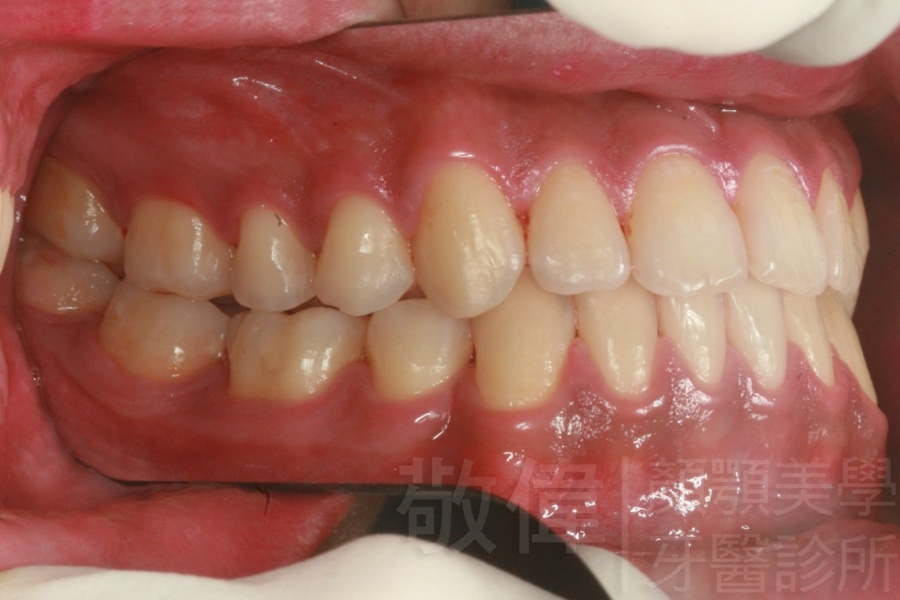

齒顏矯正/上顎暴牙且牙齒極度混亂

矯正前-右   矯正前-正   矯正前-左

矯正後-右   矯正後-正   矯正後-左

<個案說明>

上顎暴牙且牙齒極度混亂,經由矯正之後,臉型大幅度改善,牙齒的排列更加的整齊健康。相較於之前眼神充滿精神,自信心展現無遺。